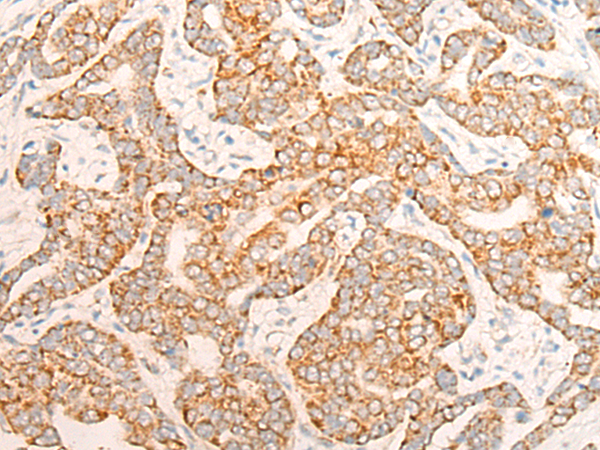

The image is immunohistochemistry of paraffin-embedded Human liver cancer tissue using P13127(ALDH7A1 Antibody) at dilution 1/20. (Original magnification: ×200) |